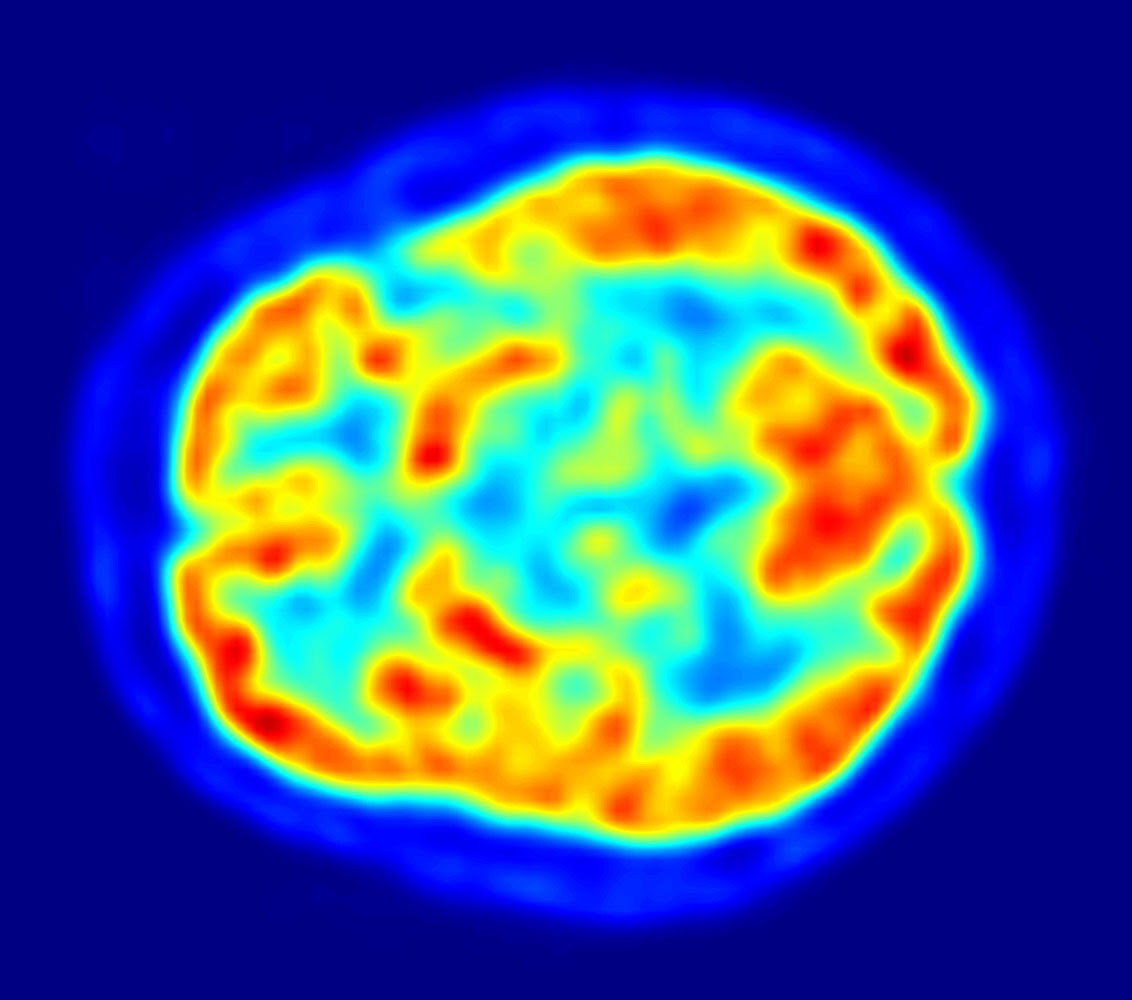

Tumeur du cerveau wikipédia. Kinds. L'oms a produit une classification et description des cancers du cerveau [1] qui a varié de 1979 à 2007, los angeles type los angeles plus récente étant celle de. Cancer du cerveau causes, symptômes, traitement, diagnostic. Traitements du cancer. Le traitement du cancer est adapté en fonction de chaque scenario. En effet, chaque patient atteint d'un most cancers est un cas particulier et. We did no longer discover effects for tumeur au cerveau wikipedia. La radiofréquence dans le traitement du most cancers du. · platech intervenants pr olivier seror radiologie interventionnel carrier d'imagerie médicale hôpital jean verdier m. Clément. Take a look at spelling or type a brand new question.